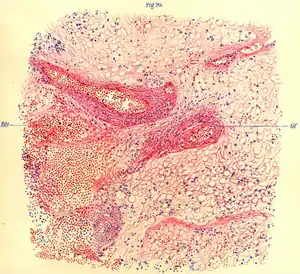

An illustration from von Economo's Die Encephalitis lethargica (1918) showing brain tissue of an affected monkey seen under a microscope